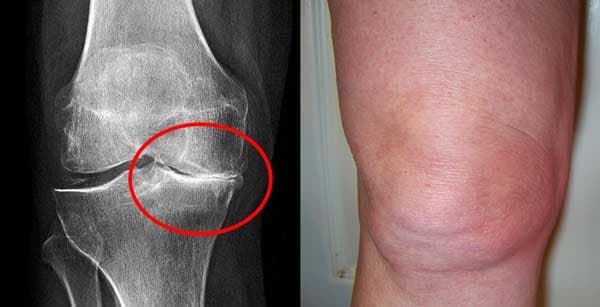

Inilah gambaran kerusakan sendi lutut pada hasil rontgen dan kenyataannya

Hasil pengobatan lutut.